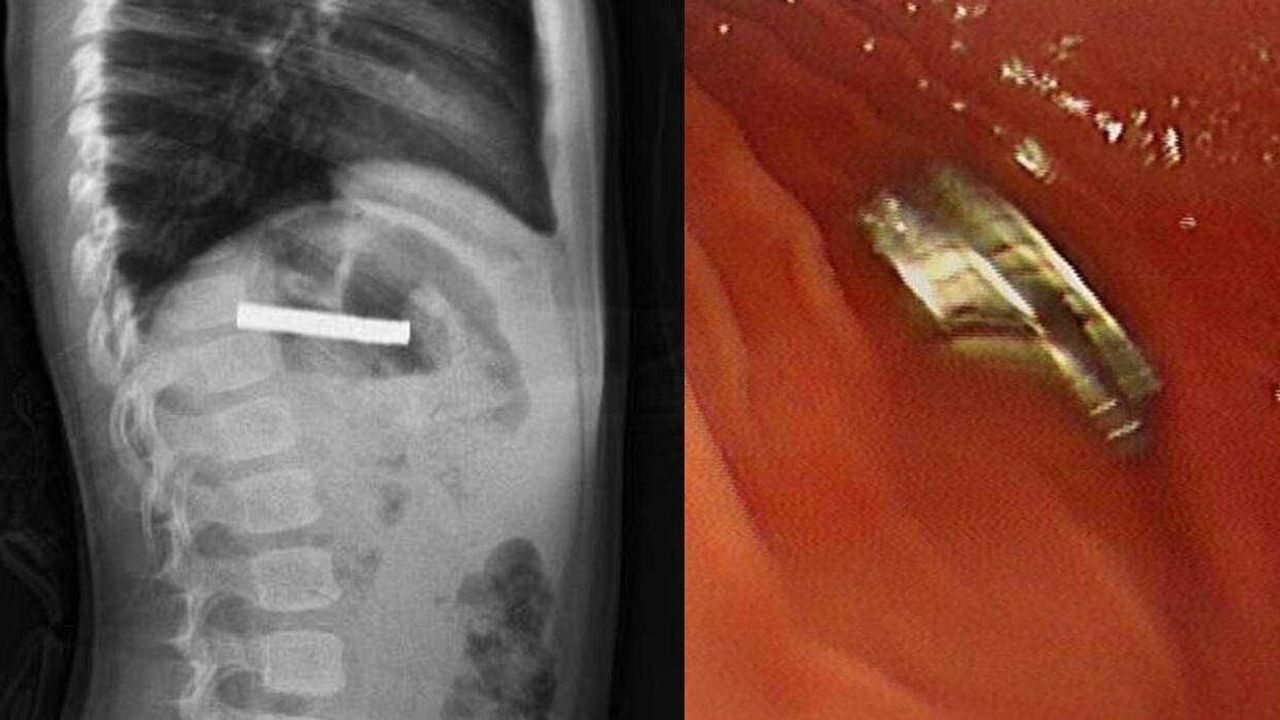

Fırat Üniversitesi Çocuk Gastroenteroloji Hepatoloji ve Beslenme Bilim Dalı Başkanı Prof. Dr. Yaşar Doğan, çocuk hastanın yemek borusuna yapışmış 19 mıknatısı endoskopik yöntemle çıkardı.

Mıknatıslar uzun süre yemek borusunda takılı kaldığı için yemek borusu ve mide girişinde zedelenmeler olurken, çocuğun sağlık durumunun iyi olduğu ve taburcu edildiği öğrenildi.